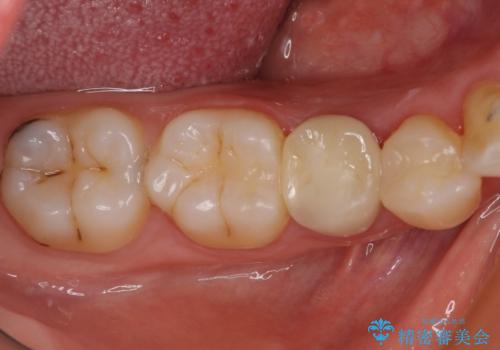

矯正治療後には、左下奥歯の症状がないことを確認し、セラミッククラウンにて補綴治療を行うこととしました。